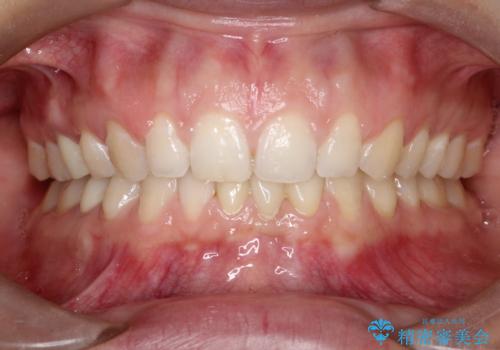

短期間での治療終了を希望され、ワイヤー矯正にて治療を行い1年ほどで治療を終了しております。

下顎前歯は矯正後補綴治療を行なっております。

期間や仕上がりで大変満足していただきました。